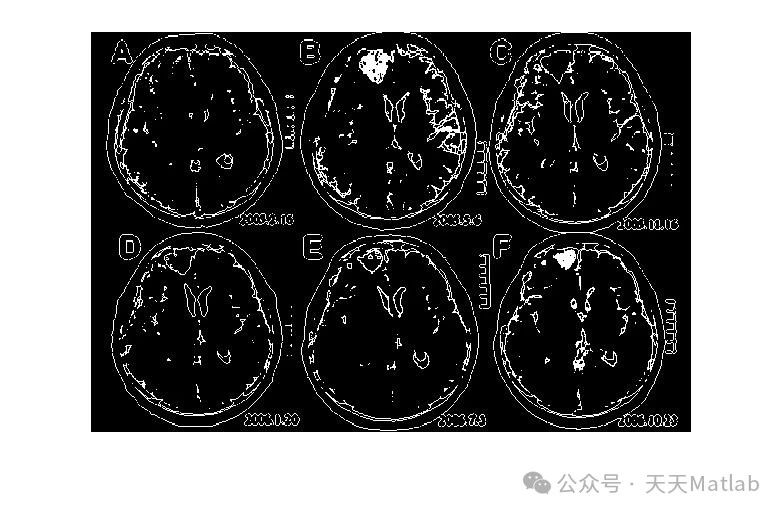

医学影像数据集则选用了公开的 MICCAI(Medical Image Computing and Computer-Assisted Intervention)脑部 MRI(Magnetic Resonance Imaging)图像数据集 。脑部 MRI 图像对于医学诊断具有重要意义,准确分割脑部组织如灰质、白质和脑脊液,能够为医生提供关键的诊断信息 。利用该数据集进行实验,可以检验算法在医学领域的应用潜力和分割精度 。

通过实验,我们得到了优化前后 PCNN 算法的分割结果图像,以及各项评价指标的数据 。从分割结果图像来看,传统 PCNN 算法在某些复杂场景下,如自然场景中物体边界模糊、医学影像中组织对比度较低以及工业检测图像中噪声干扰较大的情况下,分割结果存在较多的误分割和漏分割现象 。例如,在自然场景图像中,传统 PCNN 算法可能会将一些与背景颜色相近的物体部分误判为背景,导致物体分割不完整;在脑部 MRI 图像中,对于灰质和白质之间边界模糊的区域,传统 PCNN 算法容易出现分割不准确的情况;在工业检测图像中,噪声会干扰传统 PCNN 算法的分割结果,使得缺陷区域的分割出现偏差 。

相比之下,经过 NSGAII 优化后的 PCNN 算法在分割效果上有了显著提升 。在自然场景图像中,优化后的算法能够更准确地识别物体的边界,将物体从复杂的背景中完整地分割出来;在脑部 MRI 图像中,对于灰质、白质和脑脊液的分割更加精确,能够清晰地区分不同组织之间的边界;在工业检测图像中,优化后的算法对噪声具有更强的鲁棒性,能够准确地分割出产品表面的缺陷区域 。